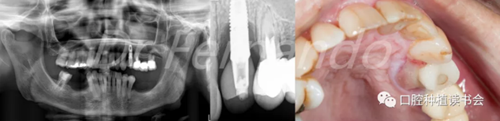

患者為64歲女性,大約在5年前在24位點(diǎn)植入種植體,近期感覺種植體有疼痛不適,相應(yīng)的上腭部位有明顯的病變(圖 19-右 )。

圖19 24種植位點(diǎn)腭側(cè)可見明顯腫脹,X片顯示明顯骨吸收

完成影像診斷檢查(曲面斷層和根尖X片)后,我們發(fā)現(xiàn)24種植位點(diǎn)存在很大的骨缺損,大約為種植體長(zhǎng)度的40%(圖19-左),探診深度大于6 mm。